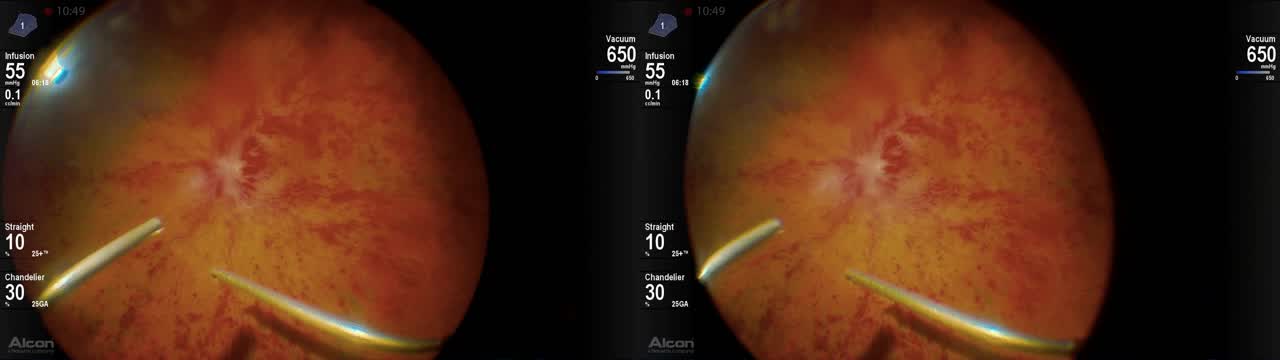

Vitreous Hemorrhage: Chicken or the Egg?

John B. Miller, MD; Christina Y. Weng, MD, MBA; Aleksandra Rachitskaya, MD; Alan J. Franklin, MD, PhD; and Matthew A. Cunningham, MD